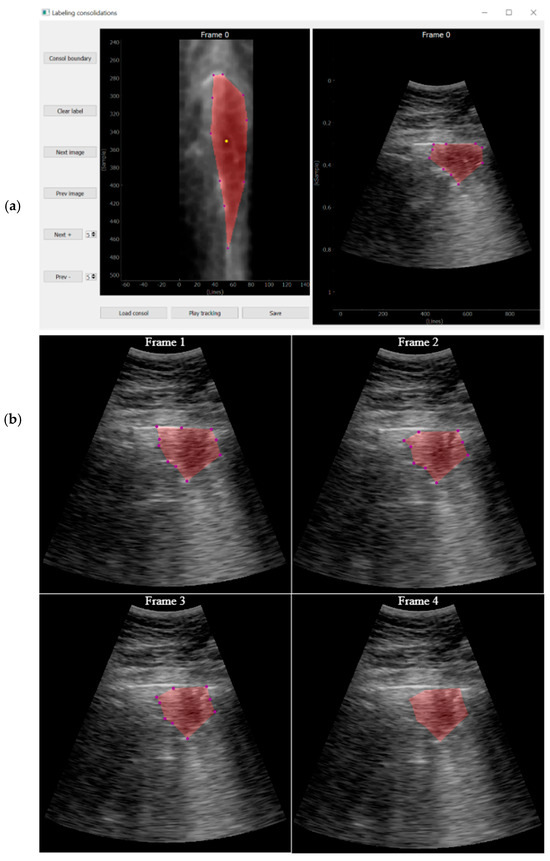

Labelling Tools